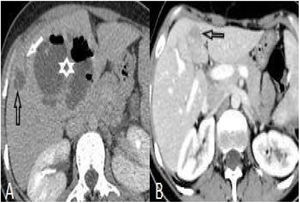

(A and B): Hepatomegaly, splenomegaly (asterisk), enlarged portal and splenic veins (black arrow), subcapsular hypodense area (circles), and intrahepatic biliary dilatation/thickening in segment VI (white arrow) in a 46-year-old woman (A). Changes of the findings on post-treatment scan are seen in (B).

The number of patients with hepatomegaly at the first admission was significantly higher than after treatment (p<.05). But the difference of the number of patients with splenomegaly was not significant (Table 2) (Fig. 1).

After treatment, the complete recovery of liver lesions was detected in 18 patients. Patchy hypodense areas were seen in 7 patients, microtubular abscess in 6 (Fig. 2), sequele calcification in 4, and abscess larger than 3cm in remained one patient (Fig. 3). The incidence of microtubular abscess and abscess >3cm was significantly lower in post-treatment images (p<.05). But, a non-significant increase in patchy hypodense area incidence was found on post-treatment images (Table 2).

Perihepatic hiperdensity was observed in 29 patients before treatment while all these lesions disappeared after treatment. At first admission, subcapsular hematoma was seen in one patient, after the treatment it regressed (Fig. 4).